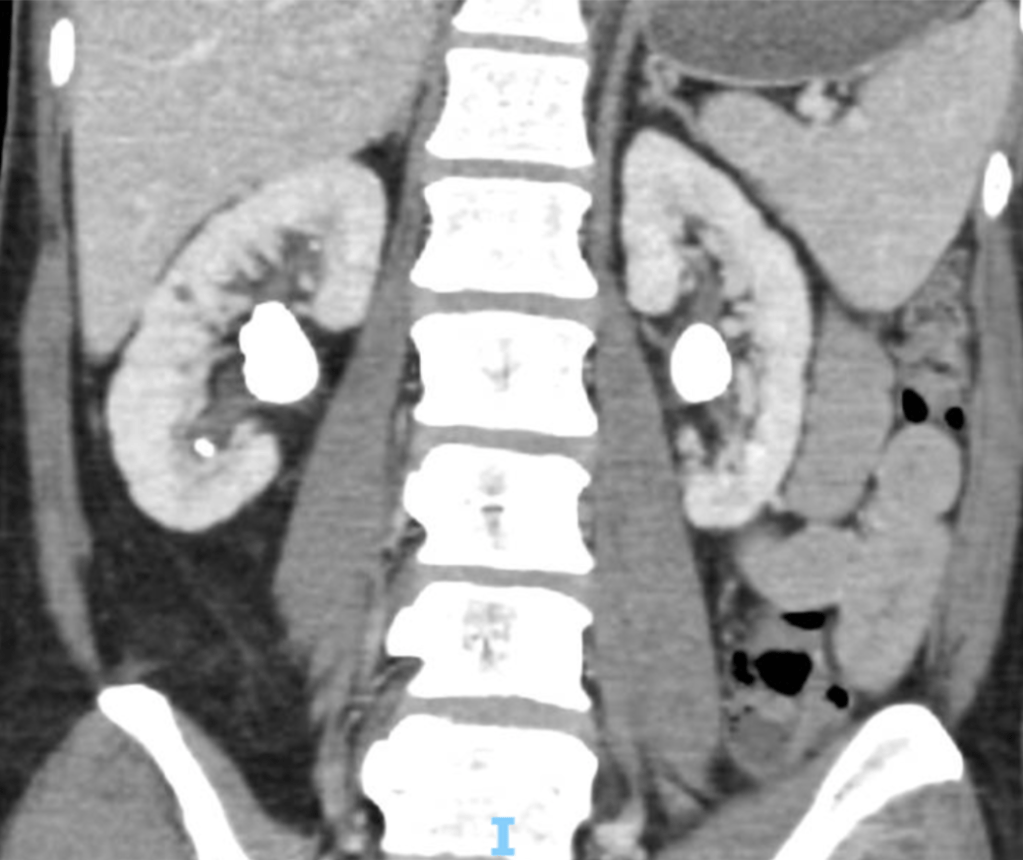

Figure 2: Bilateral Kidney Stones on CT Scan

Stones, also known as calculi, can form in any part of the urinary tract. 50% of patients presenting with a stone will develop further stones over the next 10 years. It is therefore important to try to minimise the risk of further stone formation by following certain advice.